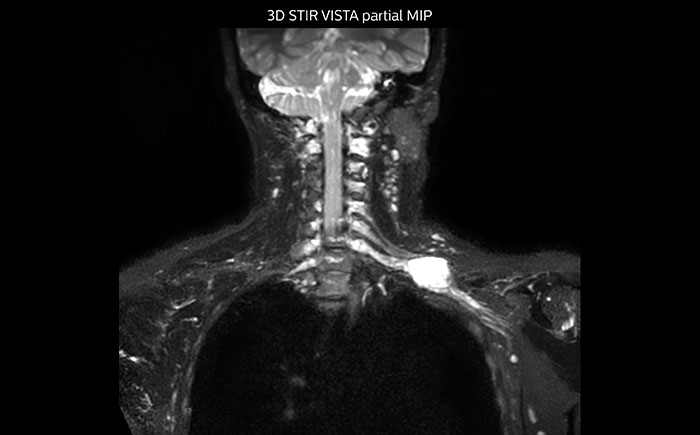

Hier handelt es sich um eine 43-jährige Patientin mit einem supraklavikulären Nervenscheidentumor links. Die Läsion ist auf den STIR VISTA Bildern und auf der MR-Neurographie mit diffusionsgewichteter MRT gut zu erkennen. Die Untersuchung wurde mit Prodiva 1.5T durchgeführt.

Erfasste Voxelgrösse: 1,2 x 1,3 x 2,4 mm, rekonstruierte Voxelgrösse: 0,7 x 0,7 x 1,2 mm, dS SENSE Faktor: 2, Scandauer: 5:46 Minuten.